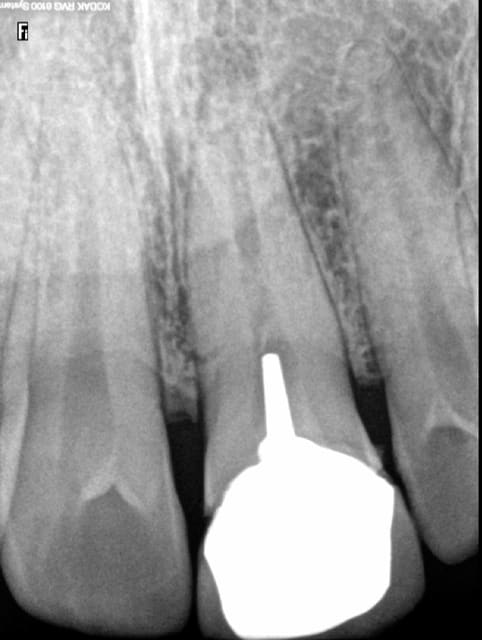

Une endo bien de chez nous juste pour le plaisir des yeux...

Notez l'ajustage du girofile

obturation à l'apex radio en mésial : très joli.

Non ca c'est rien, il y a une volonté manifeste d'aller à l'apex. -)))

J'adore la systématicité des TFM et des couronne, à la française.

Surtout sur le cliché de l'absence totale de trt endo !

Le praticien a vite facturé son tfm+ccm en se disant qu'un autre fera l'endo plus tard lol

Par contre pour l'incisive de chicot, c'est clairement du foutage de gueule. Y'en a pour 10 minutes grand max la bio là

Mais non, le gars n'a pas voulu se faire chier, honoraire pitoyable ou pas